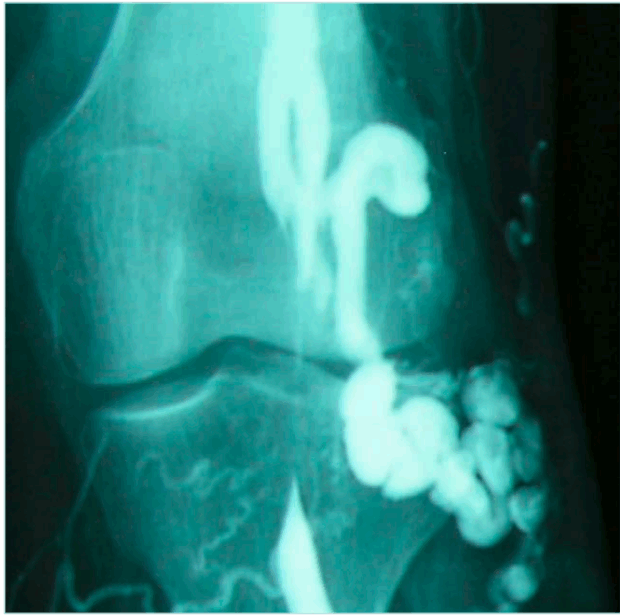

Another rare cause of venous compression is proximal tibial artery aneurysms or pseudoaneurysms, especially when the first clinical sign is leg swelling in young patients without atherosclerotic involvement. A similar case, a popliteal artery pseudoaneurysm was reported by Kim and colleagues19 in 2023. The treatment was surgical, a posterior approach with pseudoaneurysm resection and interposition of a reversed saphenous vein graft.

Here, we present a case of a 42-year-old man presenting with swelling of the right calf and pain at this level on exercise, with normal peripheral pulses. Duplex ultrasonography revealed vein compression by a pulsatile mass, filled with blood during the systole. The angio-CT suggests the diagnosis of pseudoaneurysm, which originates at the origin of the tibial posterior artery. Figure 8 shows the surgical repair by medial approach with pseudoaneurysm excision and vessel repair with autologous vein patch.